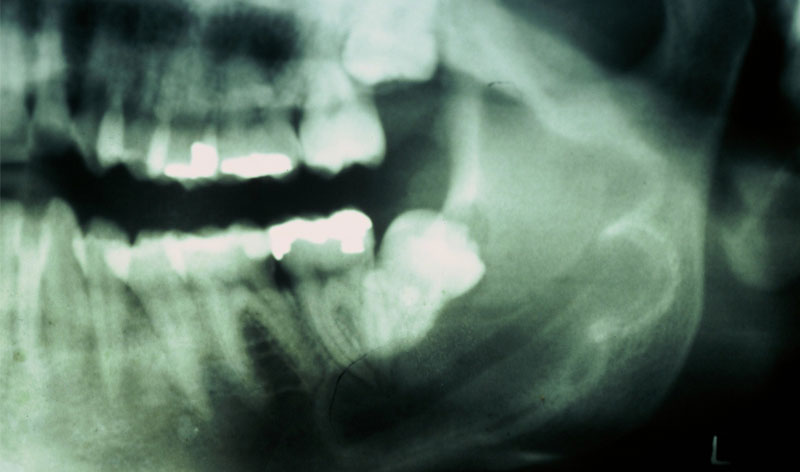

Aunque su estirpe anatomopatológica sea benigna, son quistes que en algunos pacientes provocan grandes destrucciones maxilares, porque crecen de forma asintomática durante años.